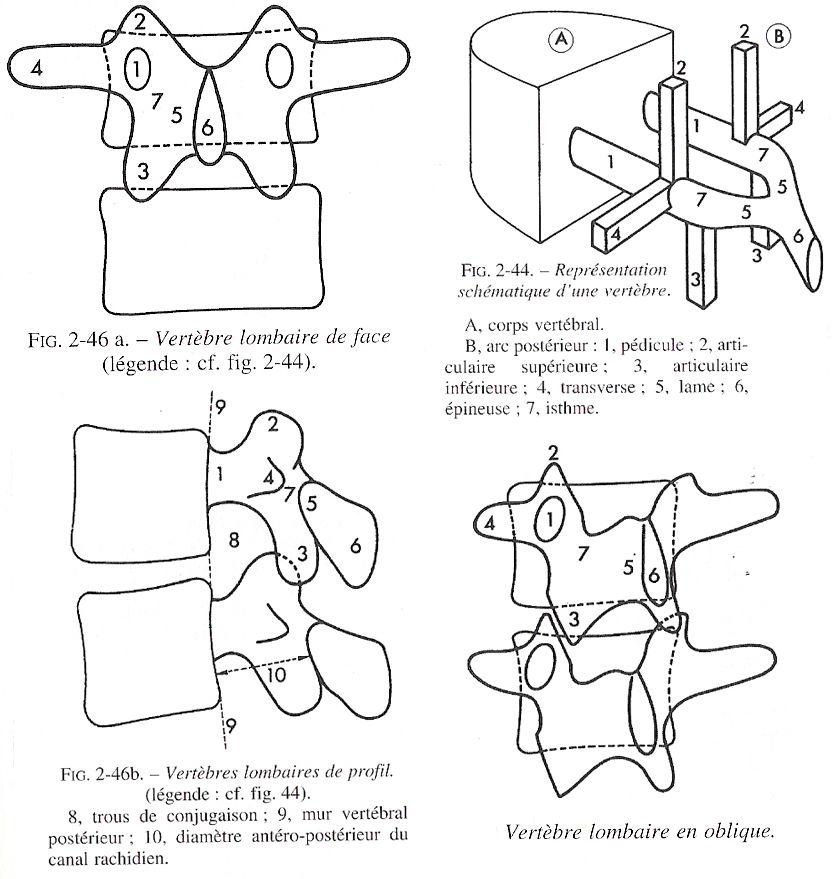

Tu peux analyser les lames sur le cliché de profil pour le rachis cervical, dorsal et lombaire ainsi que sur l’incidence de ¾ de lombaire où tu déroules les chiens de la chapelle

Rachis cervical:  Rachis dorsal: Rachis dorsal:  Rachis lombaire: Rachis lombaire:   1. Processus articulaire supérieur 2. Pédicule droit 3. Processus transverse droit 4. Isthme 5. Processus articulaire inférieur 6. Lame opposée 7. Processus transverse opposé 8. Epineuse 9. Interligne articulaire postérieure 10. Processus articulaire inférieur opposé 11. Processus articulaire supérieur opposé Pour ce qui est de la radioanatomie; nous te laissons le soin d'apprendre tout cela grâce aux livres à ta disposition et à tes stages surtout!  Nous avions commencé une liste de livres de radiologie; à toi de t'en servir et bonnes recherches! Si tu souhaites trouver d'autres correspondances, si quelques détails t'interpellent n'hésite pas à poser des questions précises! Bon courage la marmotte!